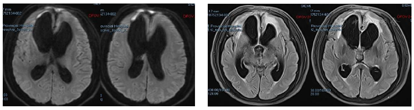

2021年9月24日患者间断高热,意识模糊较前加重,再次入院。脑膜刺激征阳性,行腰椎穿刺术,化验脑脊液提示:WBC:622×106/L,蛋白质1.34 mmol/L。脑脊液基因检测:土霉菌。行"腰大池置管外引流术",并予以伏立康唑200mg、每12小时1次,莫西沙星400mg、每日1次,利奈唑胺600mg、每8小时1次,亚胺培南1.0g、每8小时1次抗感染治疗。2021年9月27日行头颅MRI检查结果(图5)提示:脑积水,额部硬膜下及右侧脑室前角旁脓肿形成可能。2021年10月12日患者体温趋于稳定,化验脑脊液提示:WBC:77×106/L,蛋白质0.95 mmol/L。停用伏立康唑、利奈唑胺、亚胺培南,改为头孢曲松1g、每12小时1次抗感染治疗。